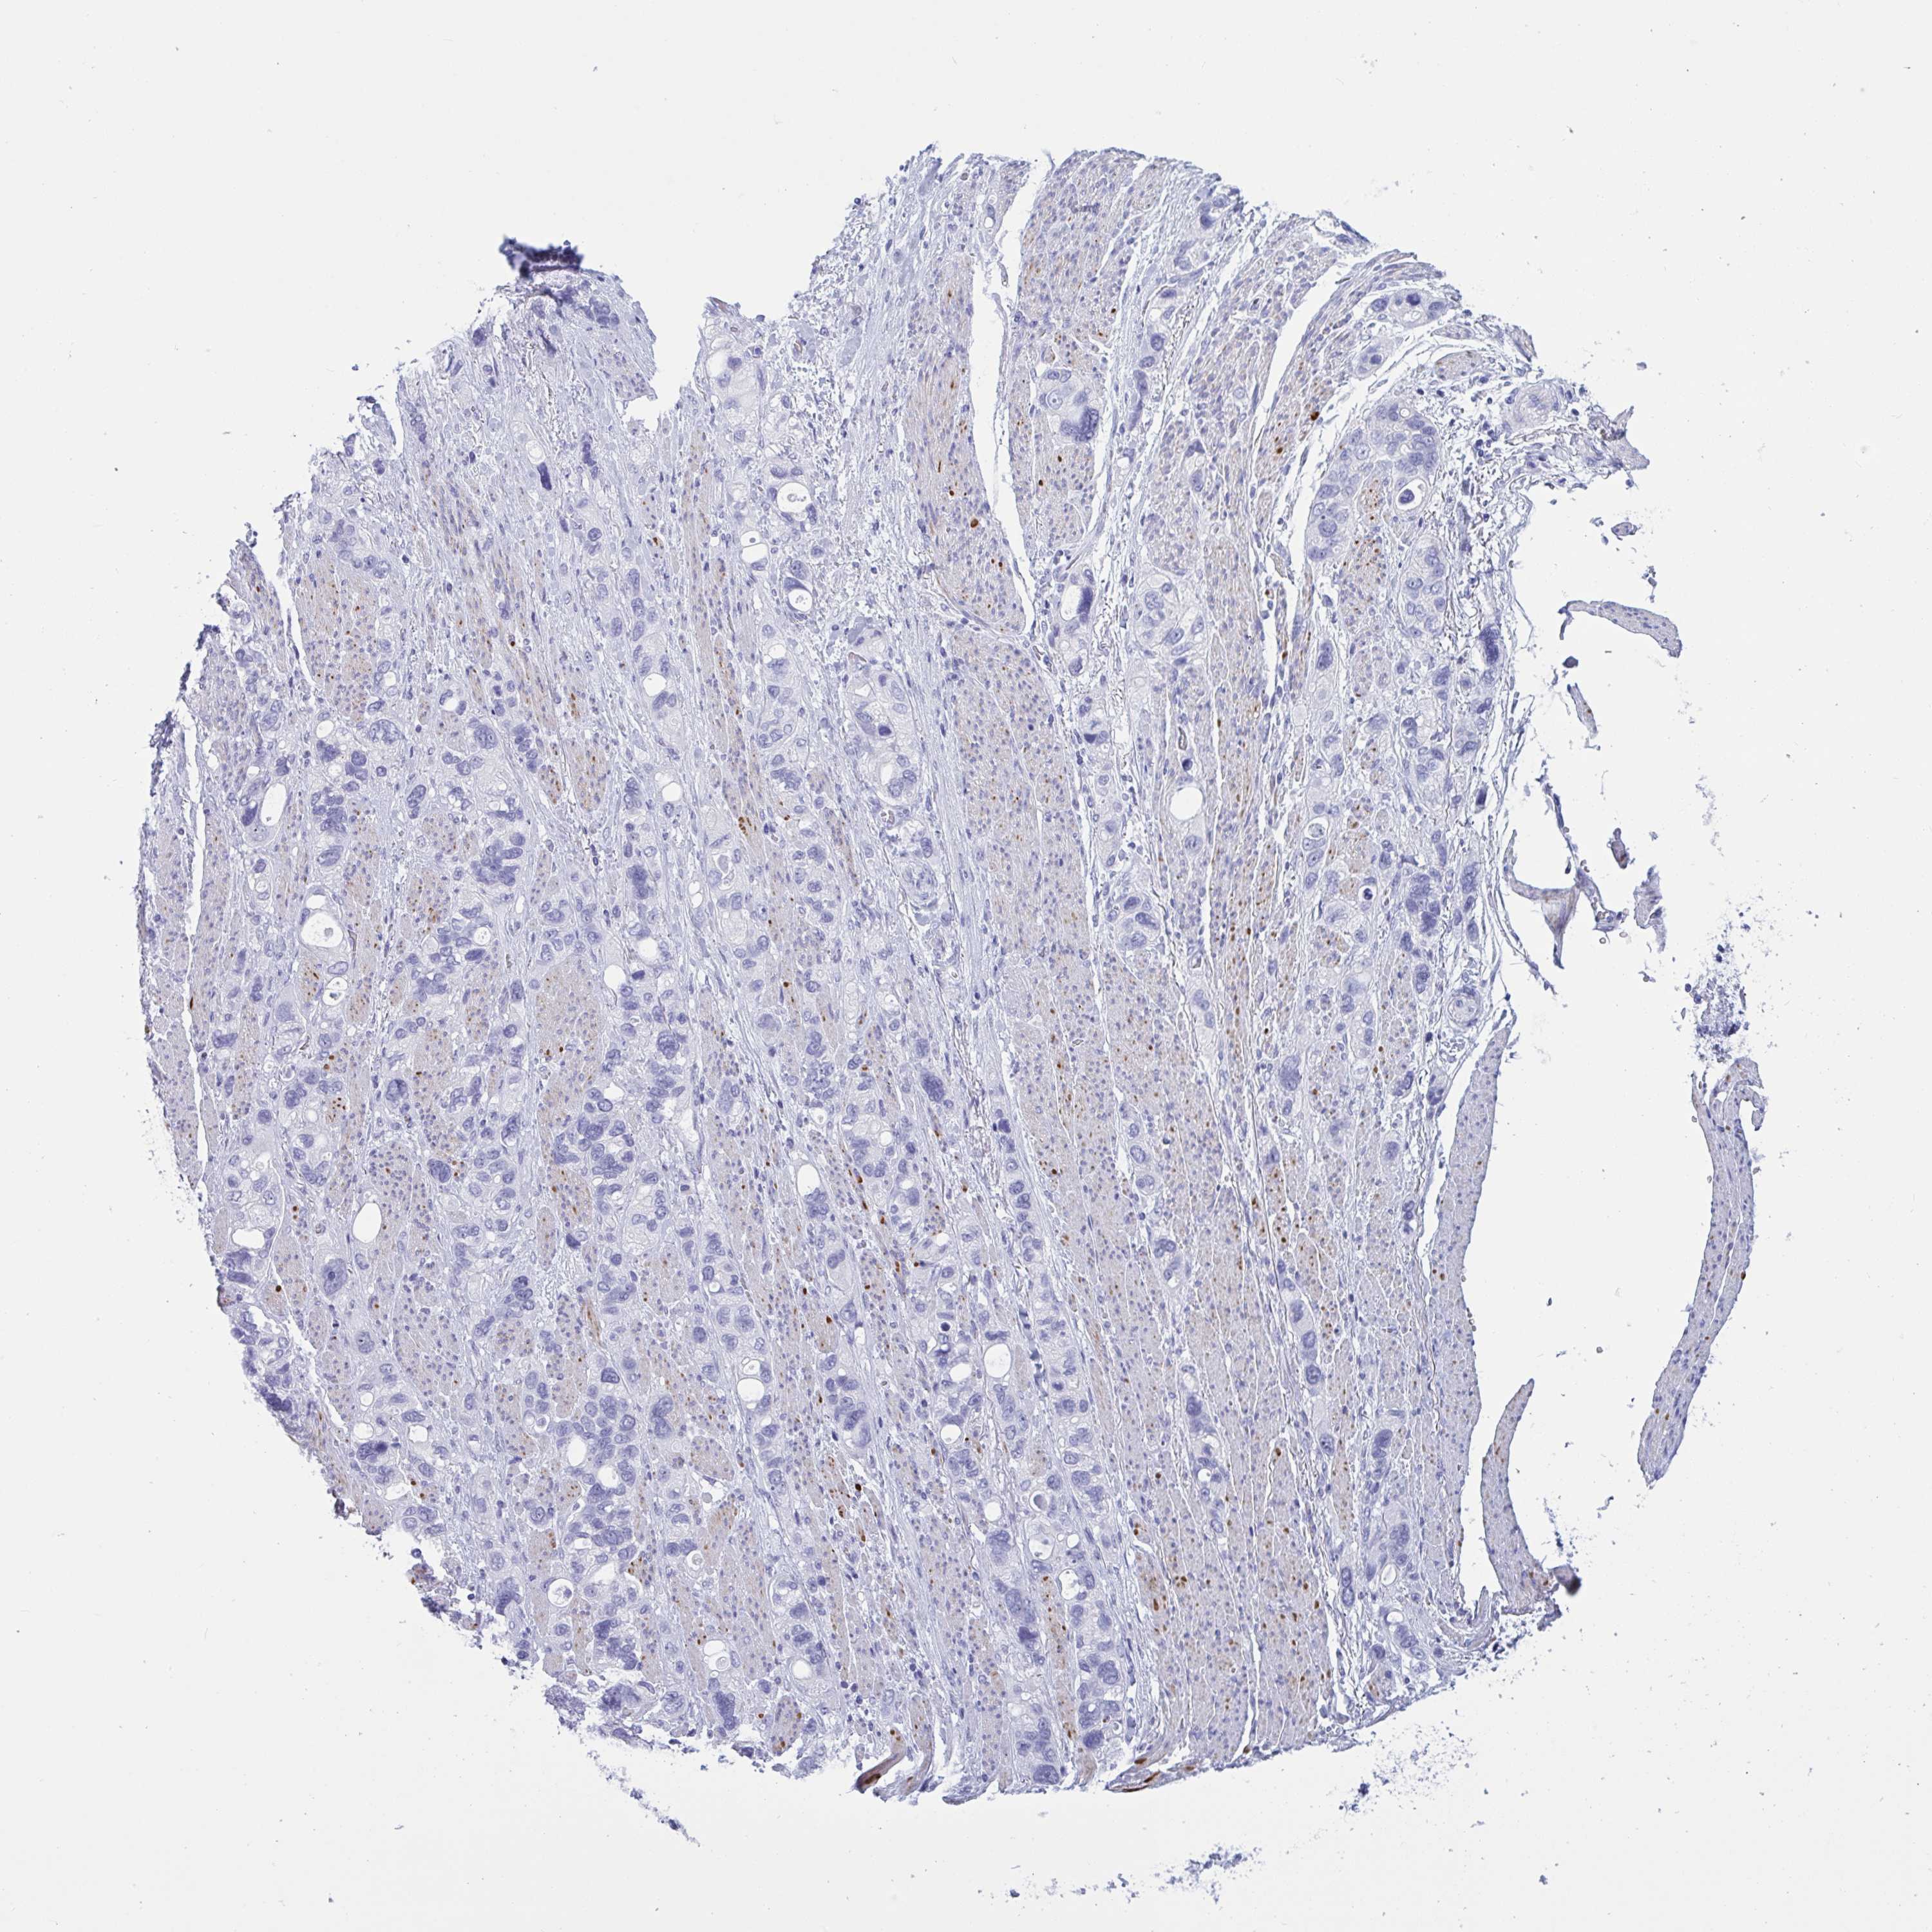

STOMACH CANCER - Protein expressioni

A mouse-over function shows sample information and annotation data. Click on an image to view it in a full screen mode. Samples can be filtered based on level of antibody staining by selecting one or several of the following categories: high, medium, low and not detected. The assay and annotation is described here.

Note that samples used for immunohistochemistry by the Human Protein Atlas do not correspond to samples in the TCGA dataset.

Antibody stainingi

Antibody staining in the annotated cell types in the current human tissue is reported as not detected, low, medium, or high, based on conventional immunohistochemistry profiling in selected tissues. This score is based on the combination of the staining intensity and fraction of stained cells.

Each image is clickable and will lead to virtual microscopy that enables deeper exploration of all samples and also displays staining intensity scores, fraction scores and subcellular localization as well as patient and tissue information for each sample.

Antibody HPA056878

Antibody HPA057019

Staining

High

Medium

Low

Not detected

Intensity

Strong

Moderate

Weak

Negative

Quantity

>75%

75%-25%

<25%

None

Location

Nuclear

Cytoplasmic/membranous

Cytoplasmic/membranous,nuclear

Adenocarcinoma, NOS